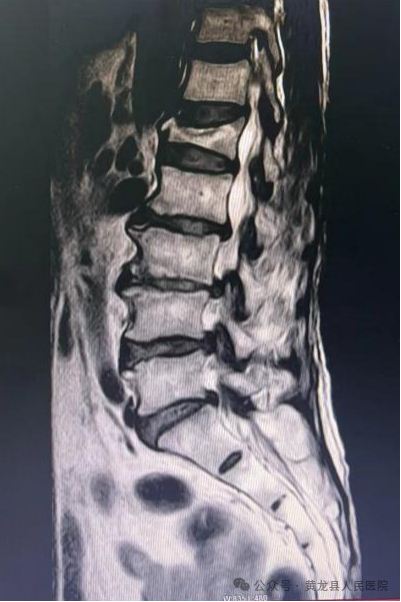

术前MRI 和术后X线影像图片

患者女,78岁,2023年3月不慎摔倒致胸腰背部疼痛,翻身、弯腰、下地活动严重受限。入院后X线检查示:腰1椎体压缩性骨折,结合患者具体情况,给予综合评估,给予微创经皮椎体成形手术,手术效果满意。2023年8月,患者再次不慎摔伤,致胸11椎体骨折,有了第一次微创手术经历,患者入院后果断选择微创经皮椎体成形手术治疗,手术顺利,达到预期效果,术后患者恢复较好,经过外科医护团队精心治疗和优质护理,患者顺利出院。患者及家属对整个就医感受很是满意,特送上锦旗向医务人员表示感谢。